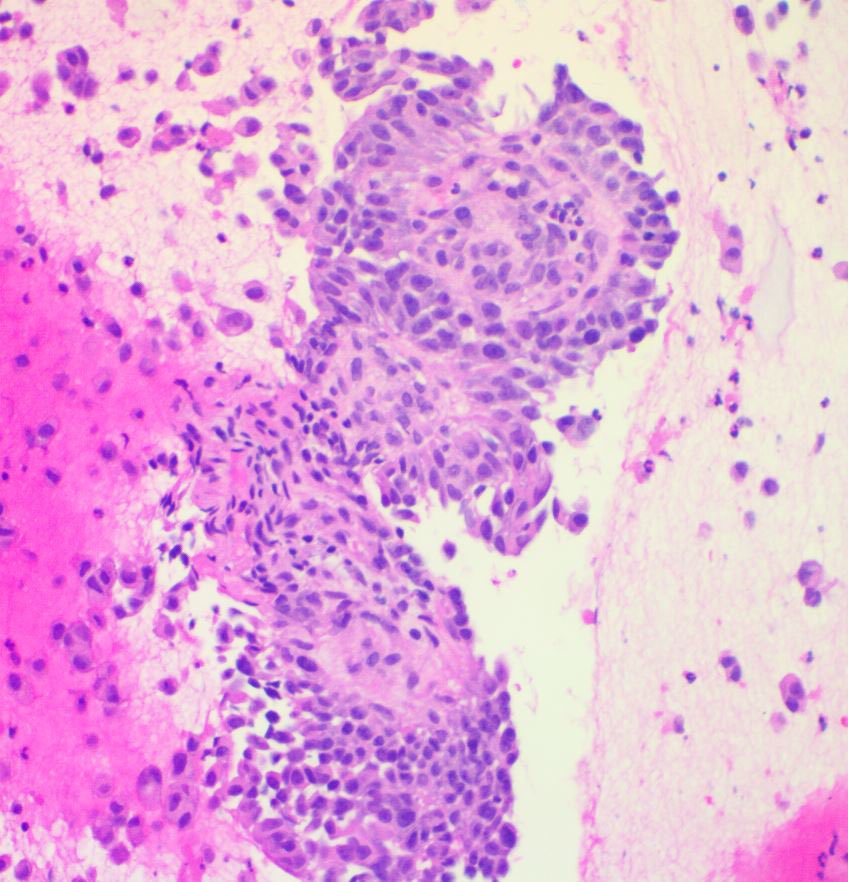

Pre-auricular nodule x 1month from 31yo patient, no other complaint. #pathtwitter #surgpath #ENTpath #hemepath #pathboards Einstein Montefiore Pathology Ridin Balakrishnan, MD Hansini Laharwani Siba El Hussein, MD Mitul B. Modi, MD Tristan Rutland MBBS FRCPA IFCAP Jerad Gardner, MD Kamran Mirza MD PhD - کامران مرزا